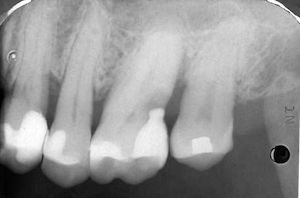

Röntgenbild: links oben ist der Mini-Weisheitszahn (Zahn Nr. 18). Rechts unten hat ein Zahn (Zahn Nr. 46) eine kleine Karies im Zahnzwischenraum.

links unten: Der Mini-Weisheitszahn hat zwei Mini-Höckerchen.

rechts: Verglichen zum Nachbarzahn (Zahn Nr. 17) wirkt der Mini-Weisheitszahn wie ein Zwerg. Er bleibt so klein, weil die Zahnkronen schon lange vor dem Durchbruch fertig gebildet sind.

Auch der andere Weisheitszahn (Zahn Nr. 28) ist ein Zwerg